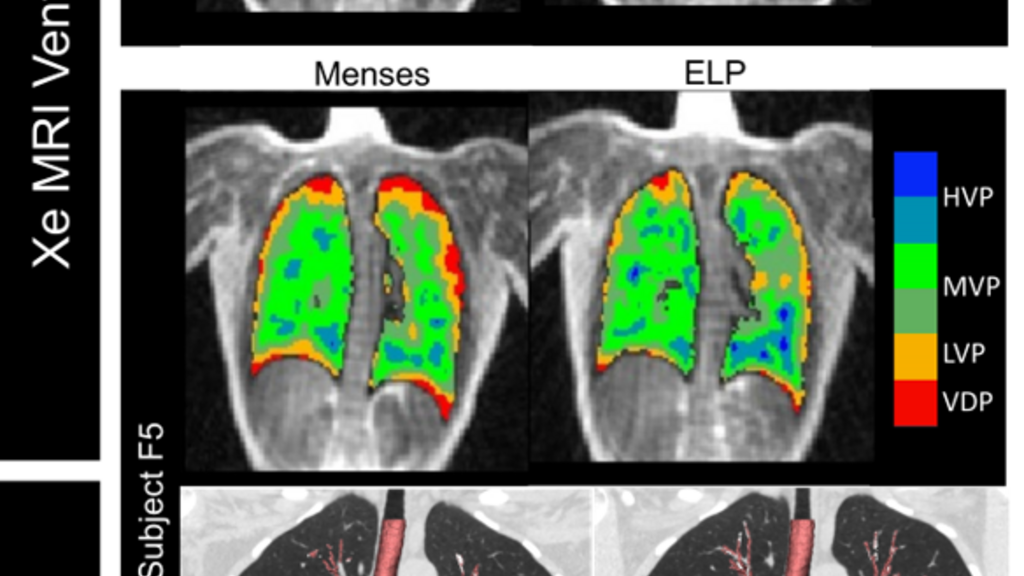

menstrual study image

Impact of the Female Menstrual Cycle on Pulmonary Disease Assessment

The goal of this research is to determine the impact of menstrual cycle related changes in the female lung on imaging biomarkers of pulmonary structure and function assessed by both multi-energy, high spatial resolution CT and hyperpolarized 129Xe MRI.